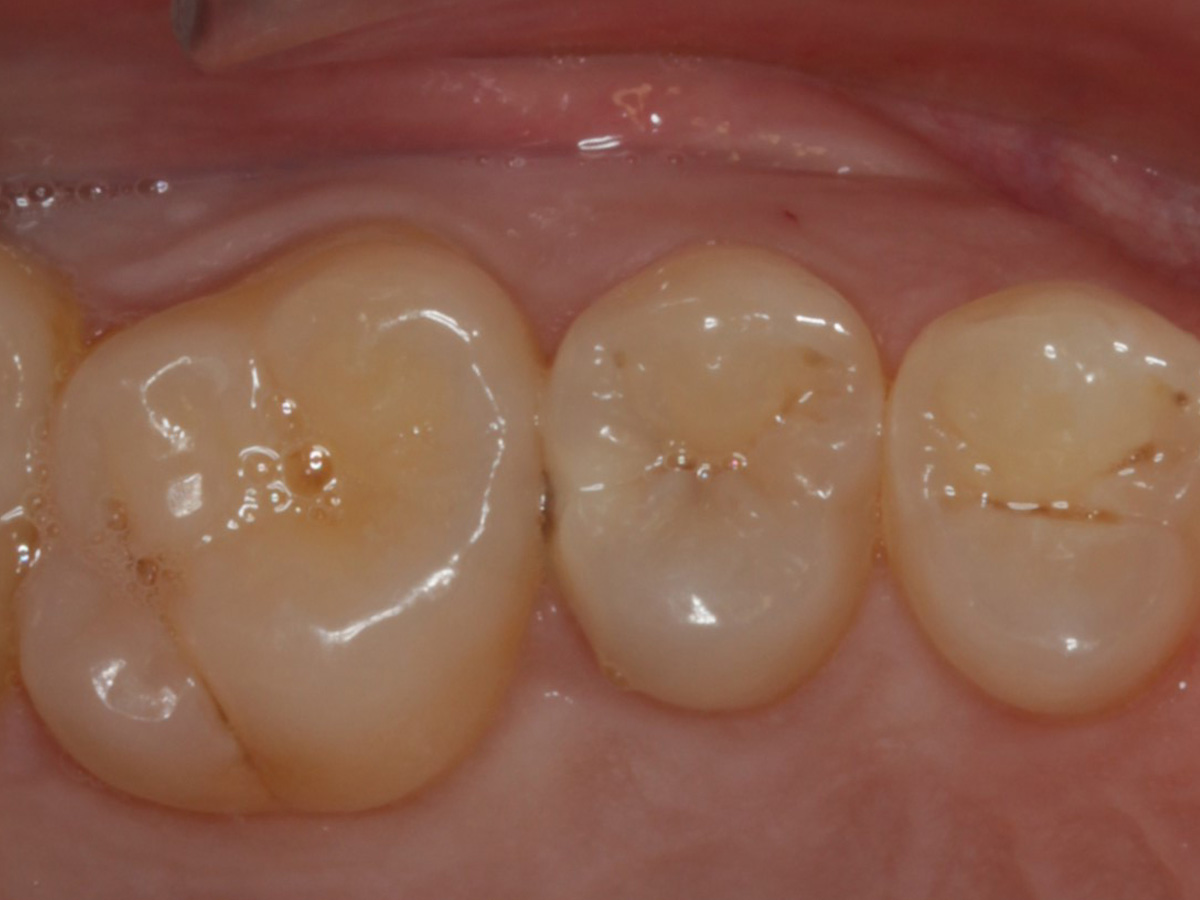

Abbildung 1

Approximalraumkaries an Zahn 25 distal